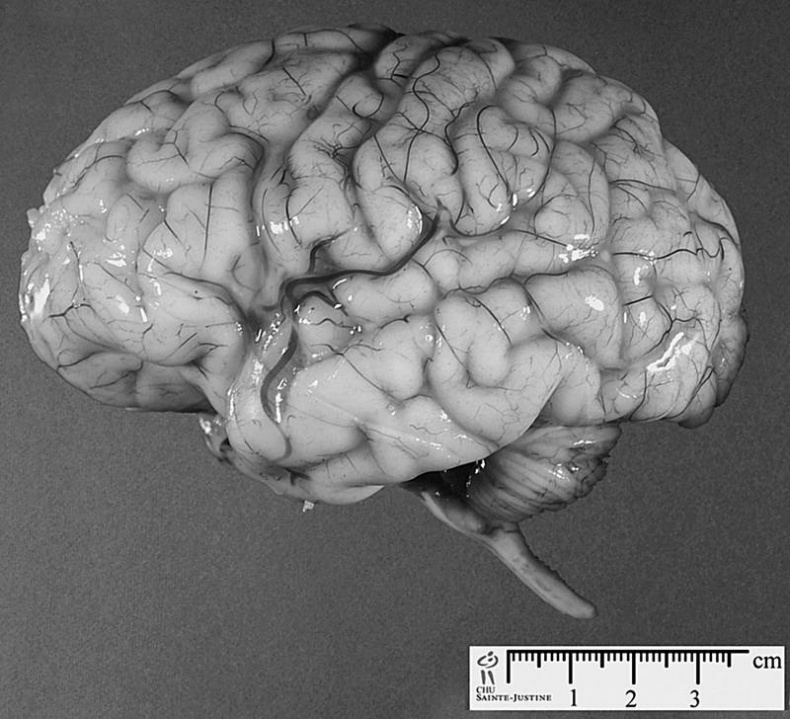

Мозг мужчины отличается от мозга женщины

Немало различий нашли исследователи и в строении мозга мужчин и женщин. Так, мозг мужчины на 150–200 граммов тяжелее женского.

Зато у женщин на 15–20 % серого вещества мозга, то есть нейронов, больше, чем у мужчин. Этот факт как раз и объясняет, почему у женщин, при меньшей массе их мозга, коэффициент интеллекта почти такой же, как и у мужчин. Просто мозг женщины в меньшем объеме содержит больше активных элементов.

А вот белого вещества, или глии, и внутримозговой жидкости в мозге мужчин больше, чем в мозге прекрасной половины. Именно глия, состоящая из покрытых изолирующей жировой оболочкой длинных отростков нейронов, позволяет четче распределять поступающую информацию между разными отделами мозга.

Правда, прямой и четкой связи между весом мозга, объемом серого вещества и глии и интеллектом мужчин и женщин не обнаружено.

Оказывается, кровь в кровеносных сосудах мозга у женщин течет быстрее, чем у мужчин, тем самым в значительной степени замедляя у них процессы старения «кладезя мудрости». Поэтому с возрастом мужчина и теряет мозговых тканей больше, чем его спутница жизни. Особенно это хорошо заметно на томограмме мозга 45-летнего человека.